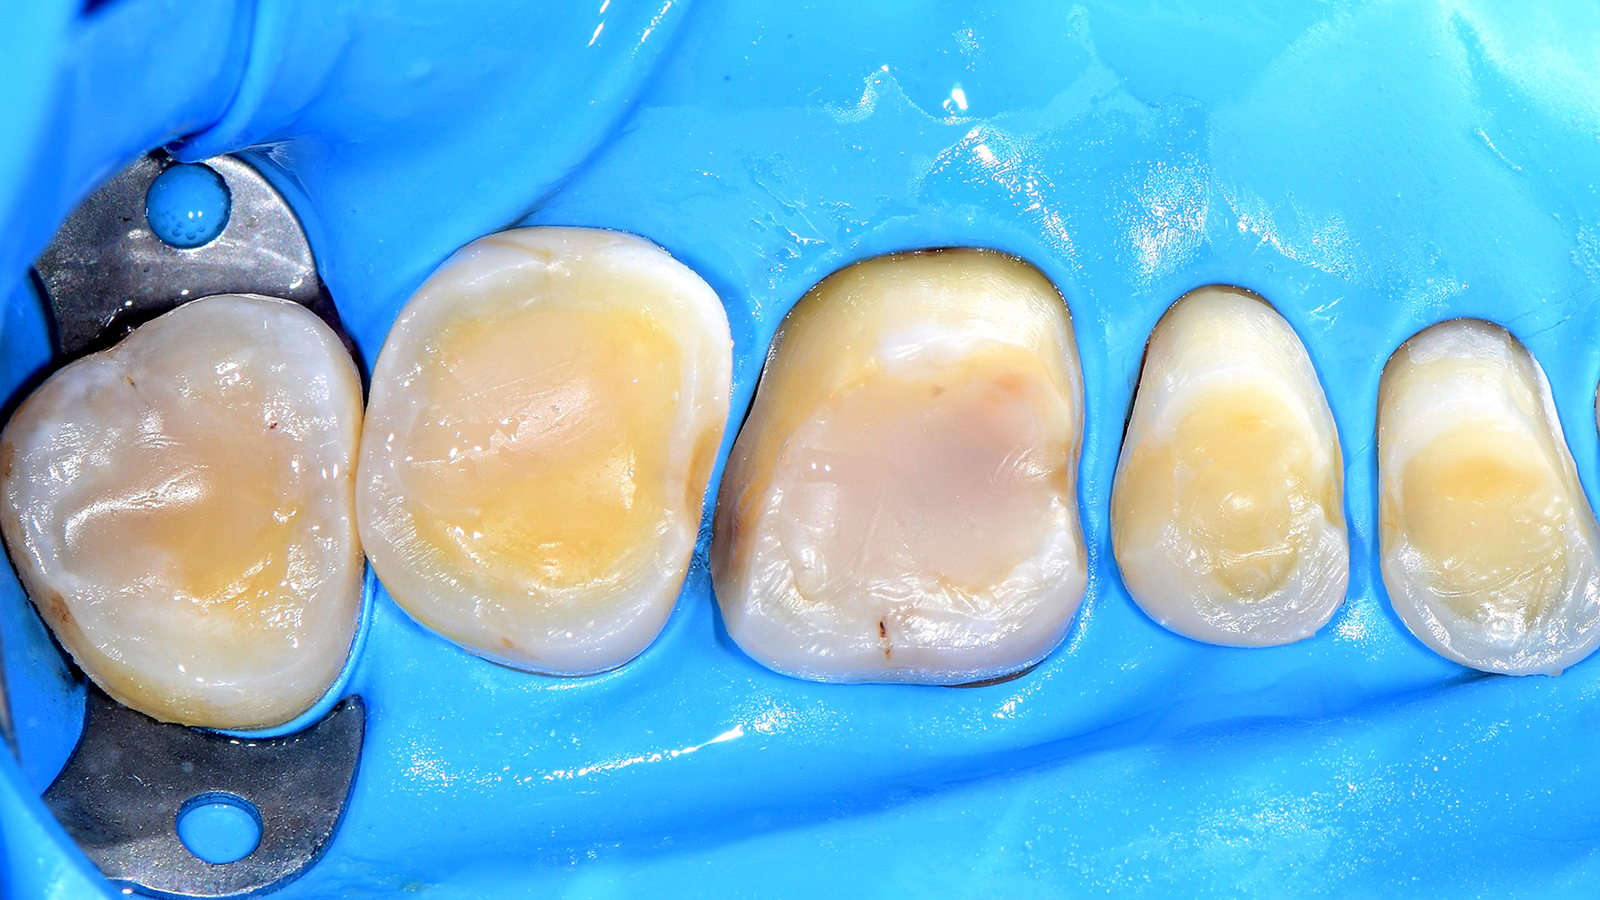

A high-viscous composite such as Charisma Diamond or Charisma Topaz can be used as capping layer if preferred. This allows the creation of the natural morphology in the occlusion which is requested e.g. in case of big cavities or cusp replacement. Any shade can basically be used based on individual preferences. Especially the Charisma Diamond/ Charisma Topaz ONE Shade promises the same colour adaptation to the surrounding dentition like Charisma Bulk Flow ONE.

The ONE shade has been optimised to deliver the perfect balance of chroma and translucency that allows the restoration to become virtually invisible. Therefore, the ONE shade can be used with confidence in any Class I and Class II restoration. And this colour adaptation is what we call Adaptive Light Matching.

Charisma Bulk Flow ONE is a flowable bulk-filling composite with curing depths of up to 4mm whereas the high-viscous composites Charisma Classic as well as Charisma Diamond and Charisma Topaz in ONE Shade are applied in incremental layering techniques in 2mm. The different viscosities and application techniques imply different benefits complementing eachother in everyday posterior restorations.